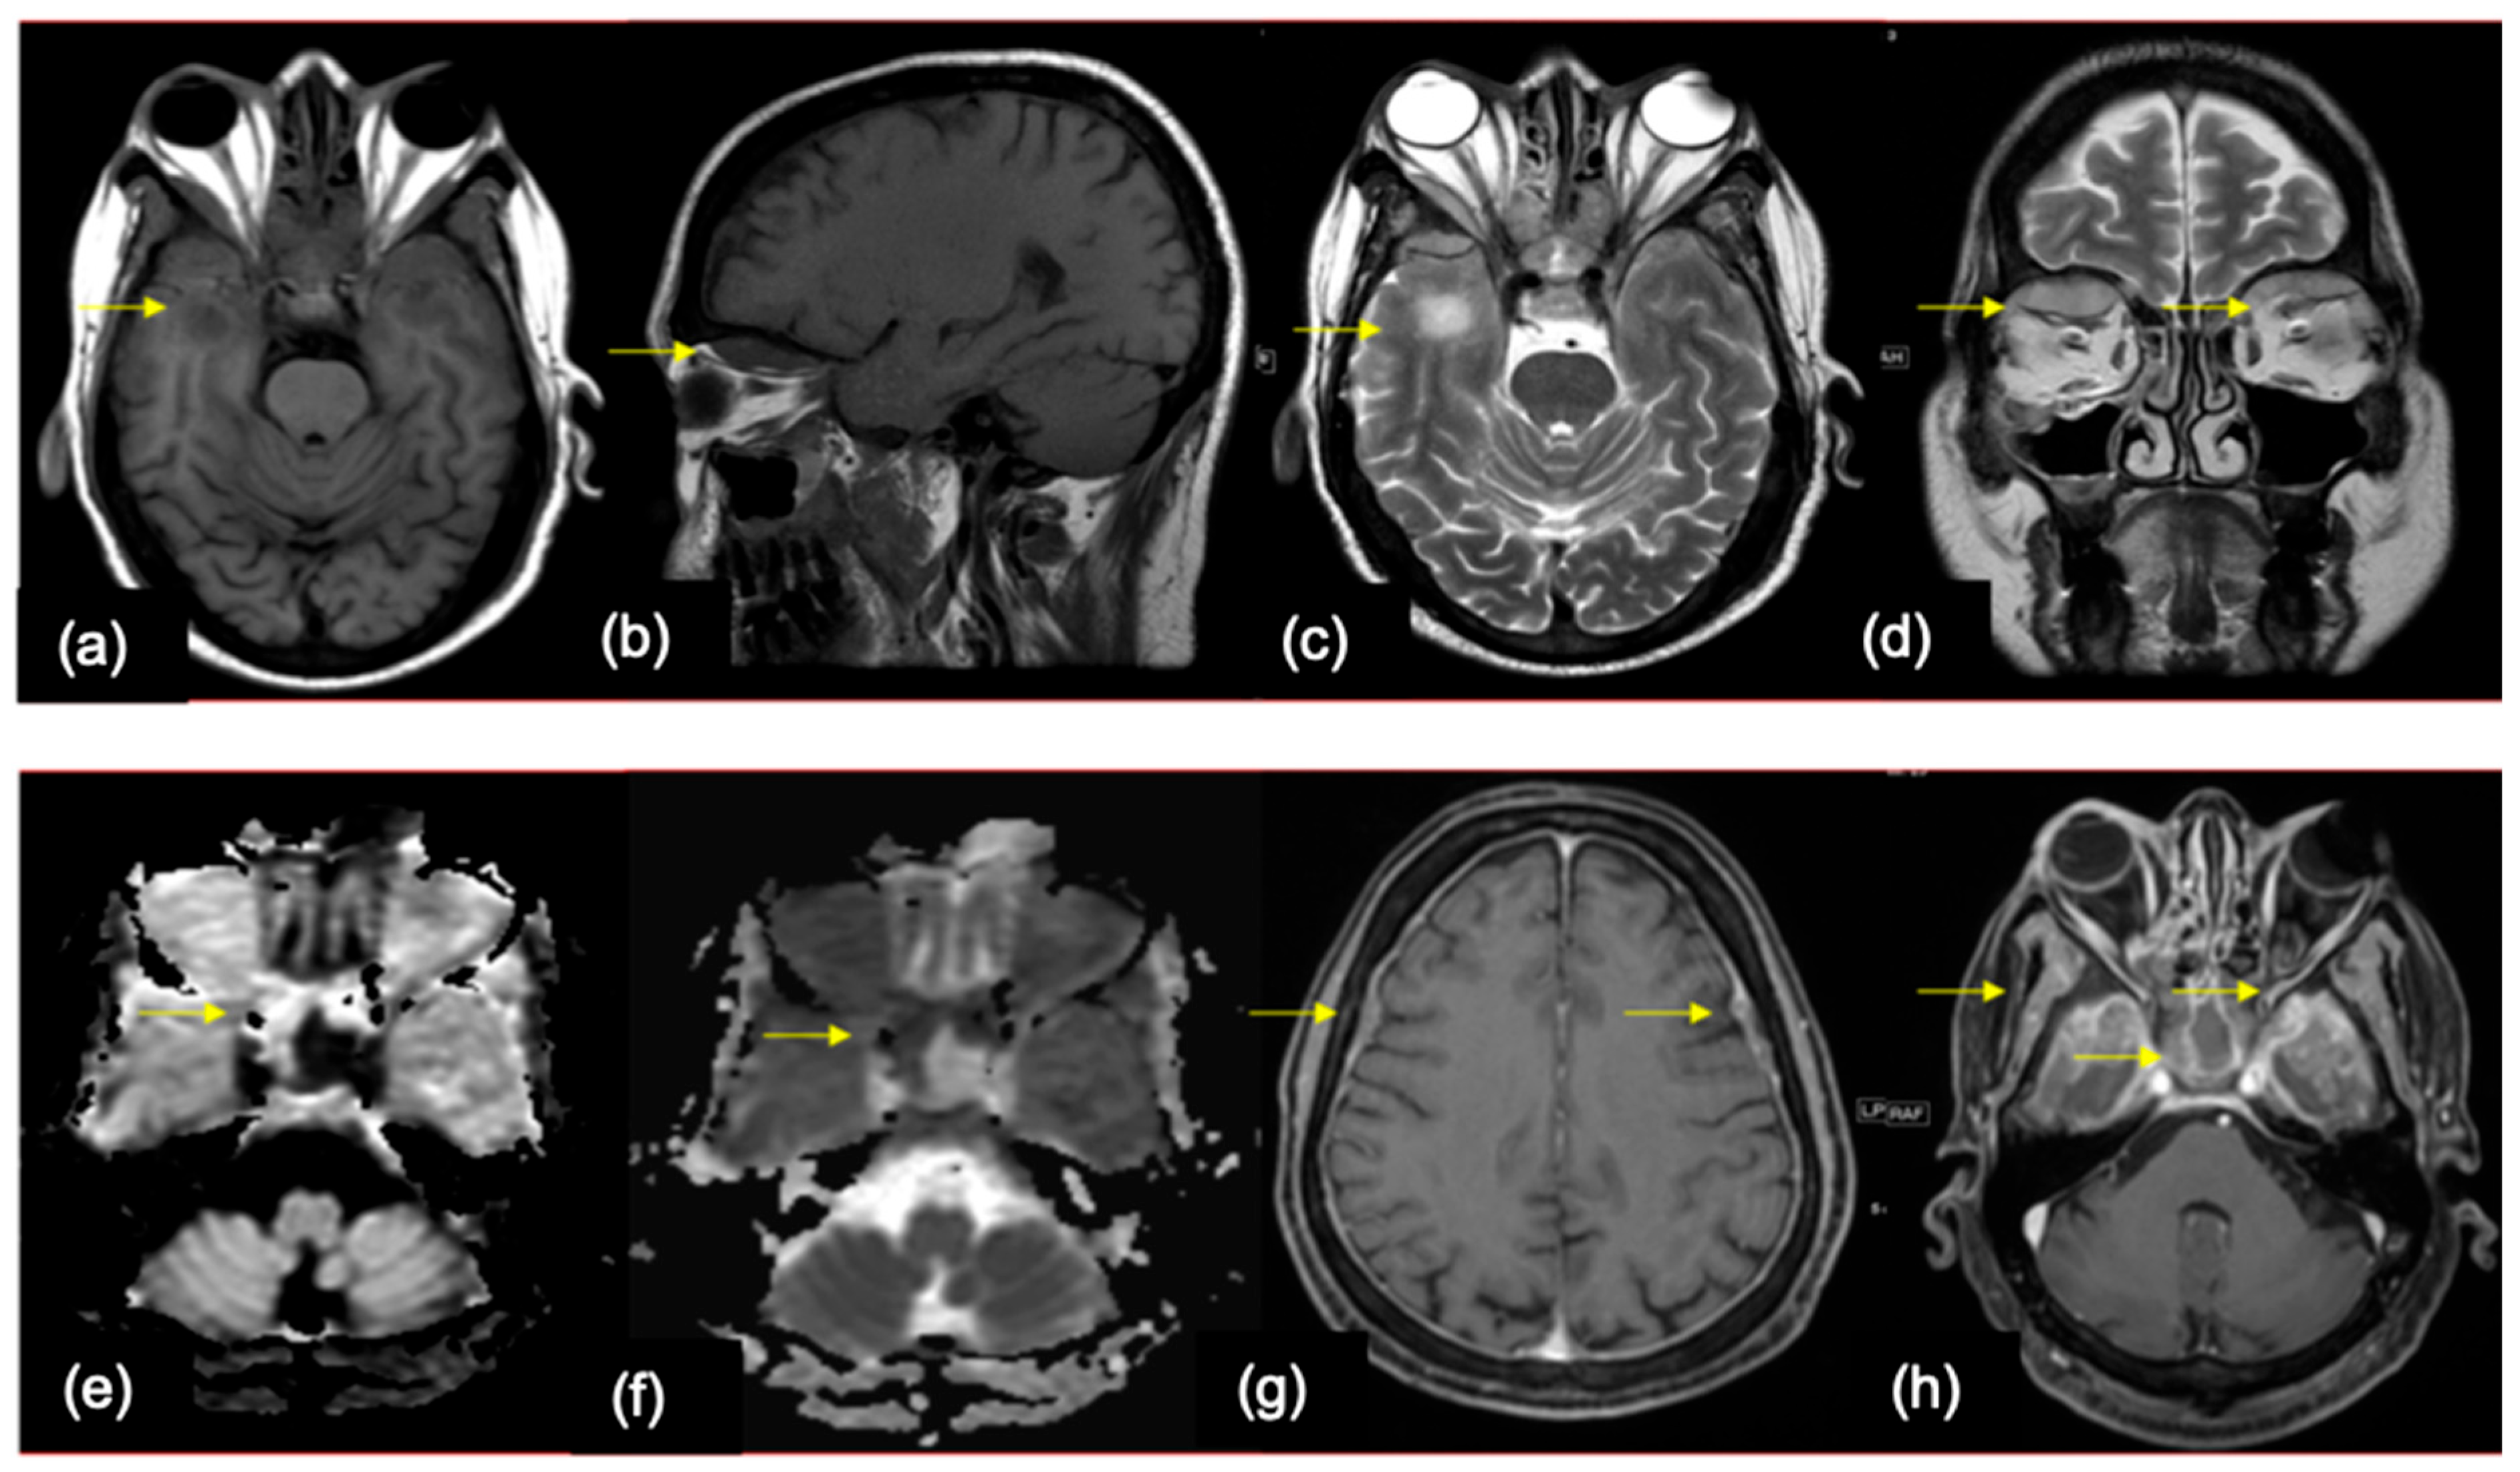

5.2. Role of Imaging in Diagnosis

7.1. Lung

7.2. Breast

7.3. Others